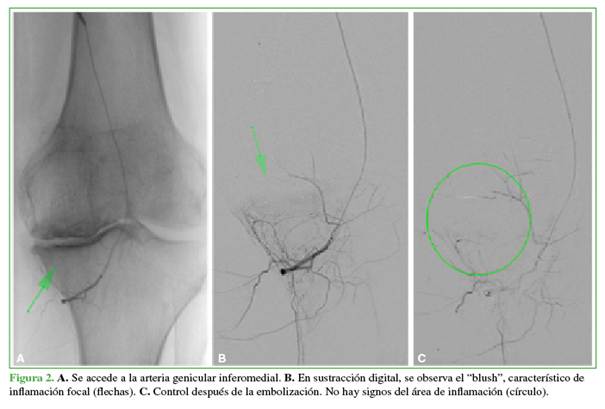

Se le propone la embolización arterial selectiva (Figura 2).

El paciente refiere franco alivio sintomático tras la embolización (Figura 3).